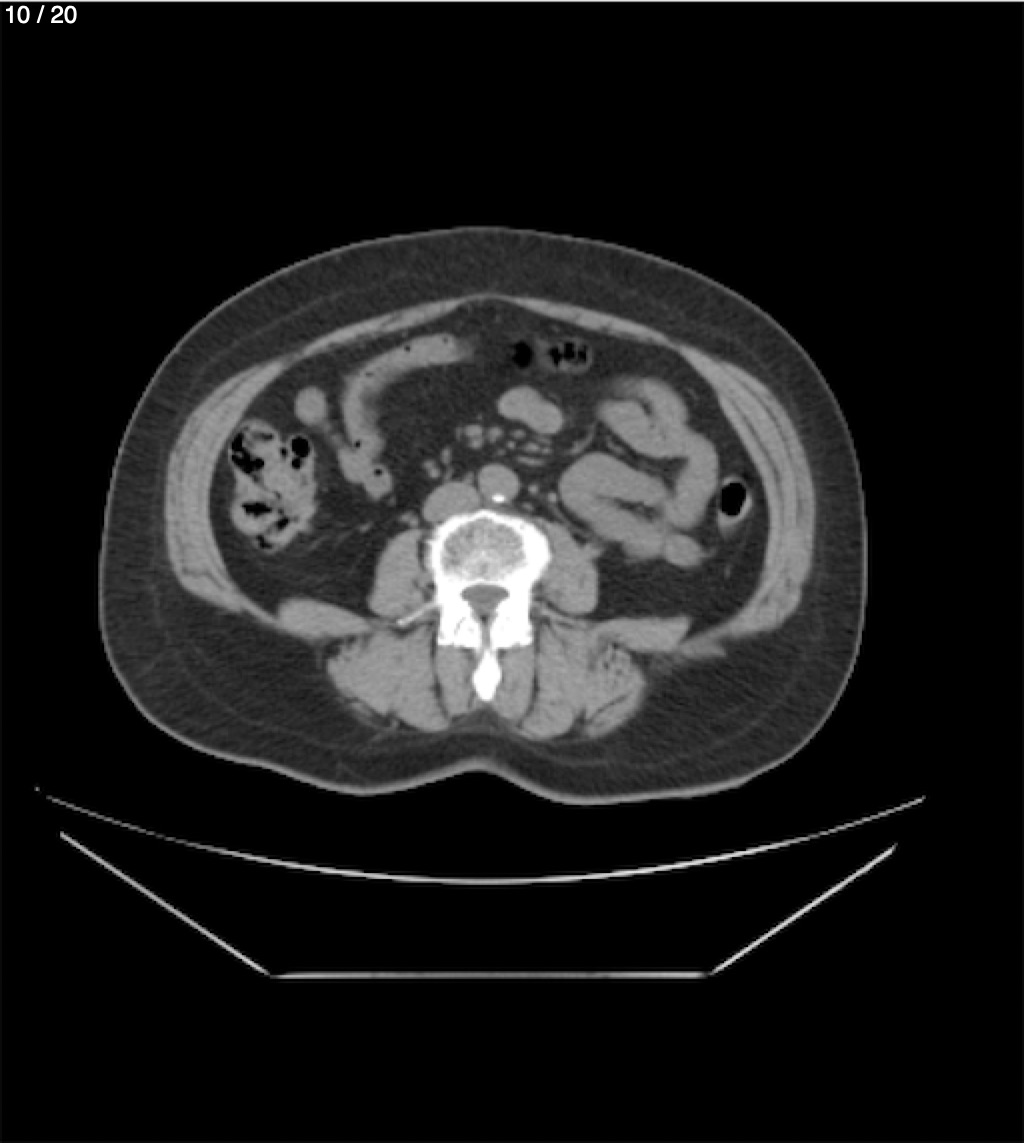

Maria Enrique Giron Dominguez63A - T.C Abdomen Simple